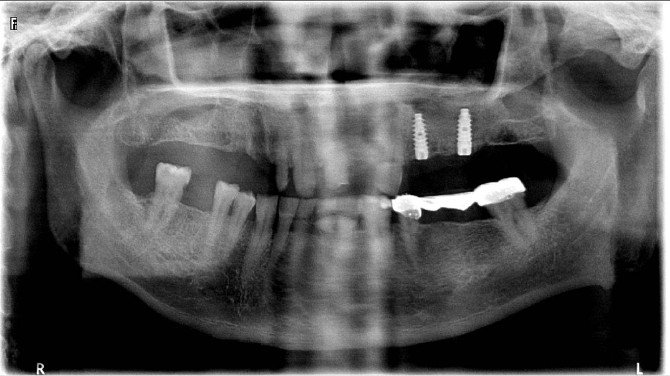

Aydın Kamu Hastaneler Birliği Genel Sekreterliği bünyesinde hizmet veren Aydın Ağız ve Diş Sağlığı Merkezinde yapılan implant uygulamalarında ileri cerrahi operasyonları (External sinüs lifting) başarılı bir şekilde uygulanmaya başladı.

Dt.Erkan Egemen Aydın Ağız Diş Sağlığı Merkezinde uygulanmaya başlanan External sinüs lifting ameliyatları ile ilgili olarak bilgiler verdi. Dt.Erkan Egemen, "Üst çenelerde, arka dişlerin üstünde maksiller sinüs adı verilen boşluklarda bulunur. Üst arka dişlerin çekilmesi sonucu, yer çekimininde etkisiyle, sinüsler kemiği eritir ve aşağı doğru sarkar. Bu durumda implant yaptırmak isteyen hastada implant için yeterli kemik kalmayabilir. Ağız Diş Sağlığı Merkezimize İmplant uygulaması için başvuran bir hastamızda karşılaştığımız sorun nedeniyle implant uygulamadan önce bu tekniği uyguladık. Şuan için hastanın genel durumu iyi. Kemik oluşumu sağlandıktan sonra da implant uygulamasını da başarılı bir şekilde uygulayacağız "dedi.